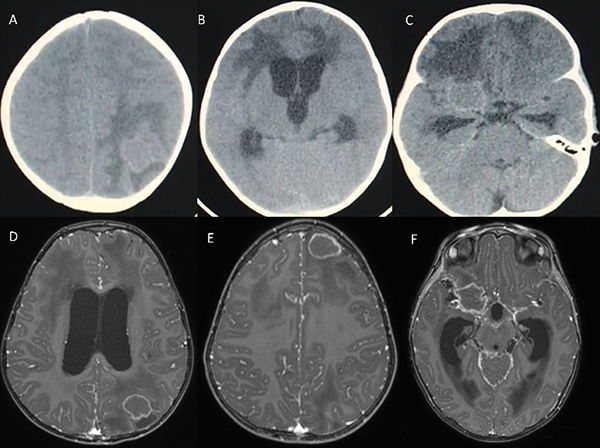

Paciente femenina de 2 años, sin antecedentes de relevancia, quien consultó en otro centro por cuadro de diarrea, vómitos y fiebre de 5 días de evolución, asociado a bradipsiquia y tendencia al sueño. A su ingreso se solicitó tomografía computada de cerebro (TC), evidenciando ventrículomegalia asociada a edema periependimario y múltiples imágenes isodensas (frontal basal derecha, frontal izquierda y parietal homolateral) con marcado edema perilesional. Se decidió realizar resonancia magnética (RMN) para caracterizar mejor las lesiones. (Figura 1)

Figura 1: A, B y C: TC de ingreso. D, E y F: RMN, secuencias T1 con contraste, se observan lesiones parietal izquierda, frontal homolateral y frontobasal derecha respectivamente. Las mismas de características cortico-subcorticales de entre 11 y 20 mm de diámetro promedio, asociadas a edema vasogénico perilesional, de bordes hiperintensos en T1 con hipodensidad central e hipointensas en T2 y Flair, con realce anular y periférico tras administración de contraste. Así mismo se observó marcado realce cisternal basal tras la administración de gadolinio.